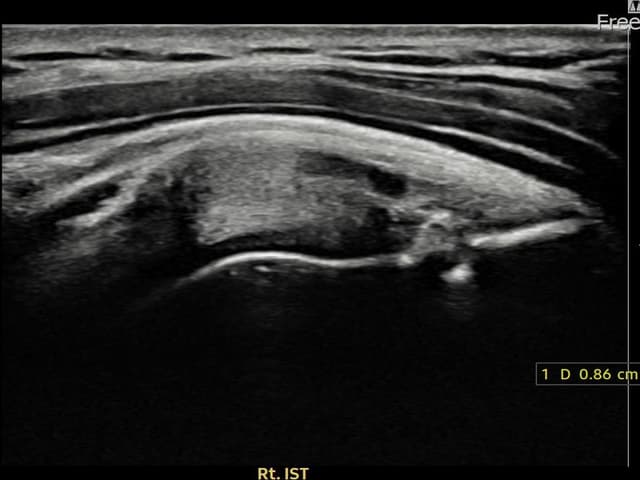

[촬영시기:22.08.13~22.10.29]

[어깨인대 축소봉합술] 우측 어깨 후방 통증과 팔을 바깥으로 돌릴 때 통증이 심해 내원하셨습니다.